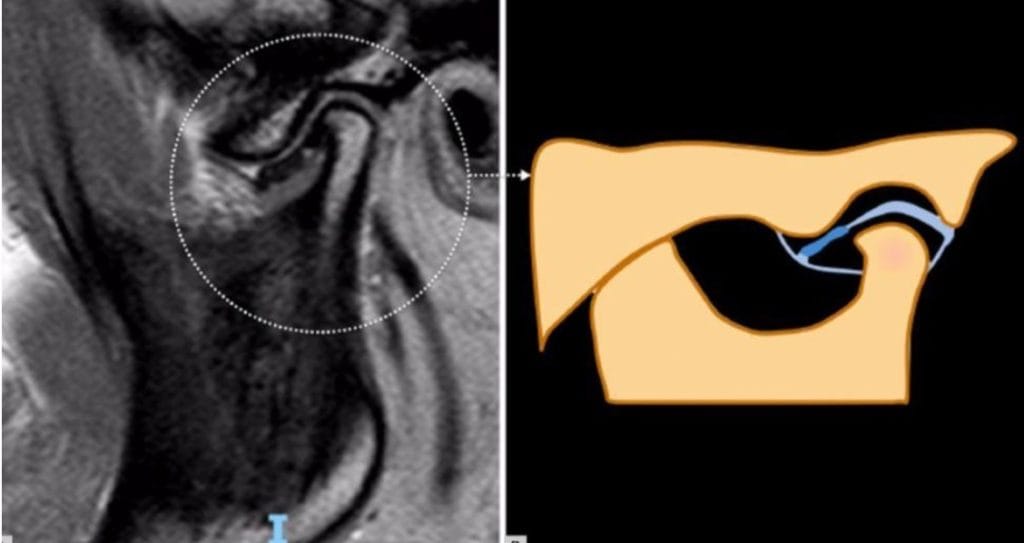

Foram identificados cinco fenótipos estruturais distintos por ressonância

magnética:

1. Adaptativo

2. Erosivo

3. Hipertrófico

4. Inflamatório

5. Ósseo

● Cada fenótipo demonstrou características específicas de sinal e alterações

estruturais nas imagens.

● Essa classificação pode melhorar a interpretação clínica da ressonância

magnética, além de orientar a seleção de intervenções terapêuticas mais

adequadas.